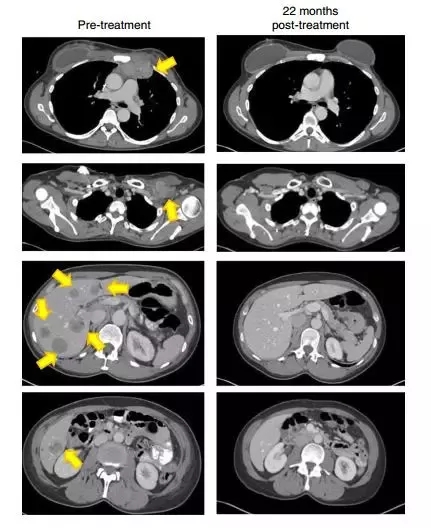

22个月后,肿瘤消失得无影无踪(图片来源:《Nature Medicine》)

一位晚期黑色素瘤患者肿瘤在治疗前出现广泛转移,在接受TILs疗法后一个月病灶明显缩小,治疗6个月达到完全缓解,治疗两年后仍然处于完全缓解状态,并且体内持续存在肿瘤反应性CD8 + T细胞。